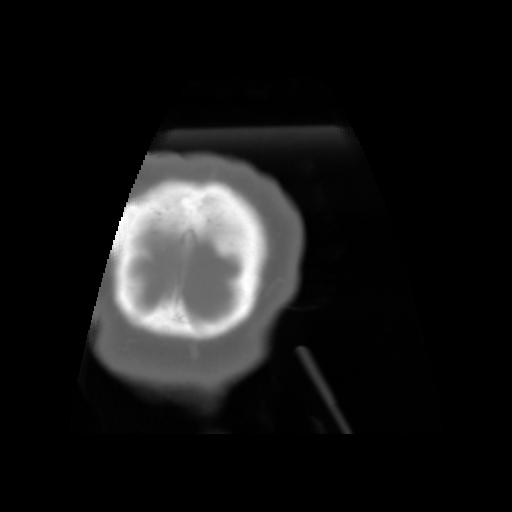

5 CEREBRO,,Coronal,3.000,CEREBRO,Coronal,